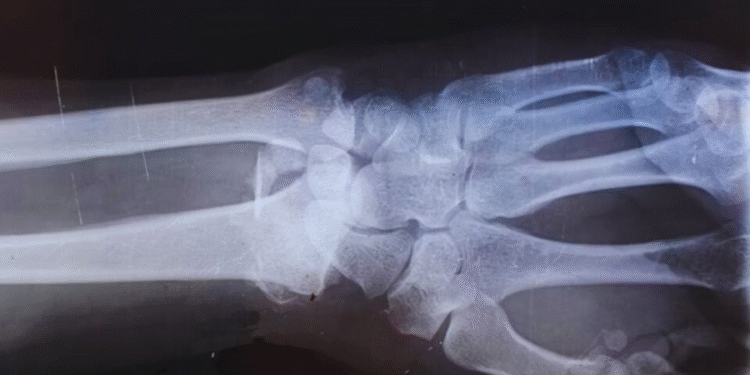

O uso da cola chinesa pode representar um avanço significativo para a ortopedia moderna. Atualmente, fraturas graves muitas vezes exigem procedimentos cirúrgicos invasivos, com implantação de materiais metálicos e posterior retirada em alguns casos. Esse processo pode gerar riscos adicionais, como infecções e complicações durante a recuperação.

Com a Bone 02, seria possível reduzir o tempo de internação e eliminar a necessidade de uma segunda cirurgia para retirada de implantes. Isso impactaria diretamente os custos hospitalares e o bem-estar do paciente. Além disso, o fato de o produto ser biodegradável garante que o corpo não precise lidar com resíduos permanentes após a cicatrização.